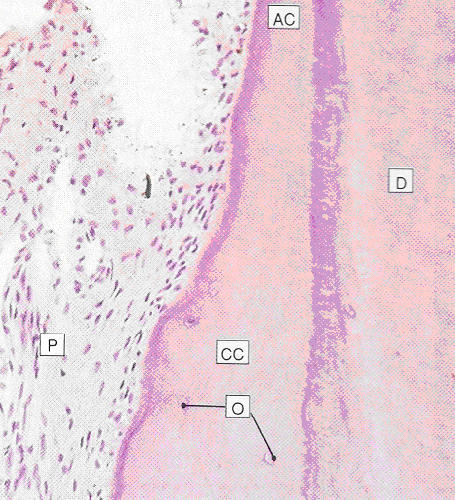

| Fig. 10.14 |

Stevens and Lowe p.150 Key: AC - acellular cementum CC - cellular cementum |